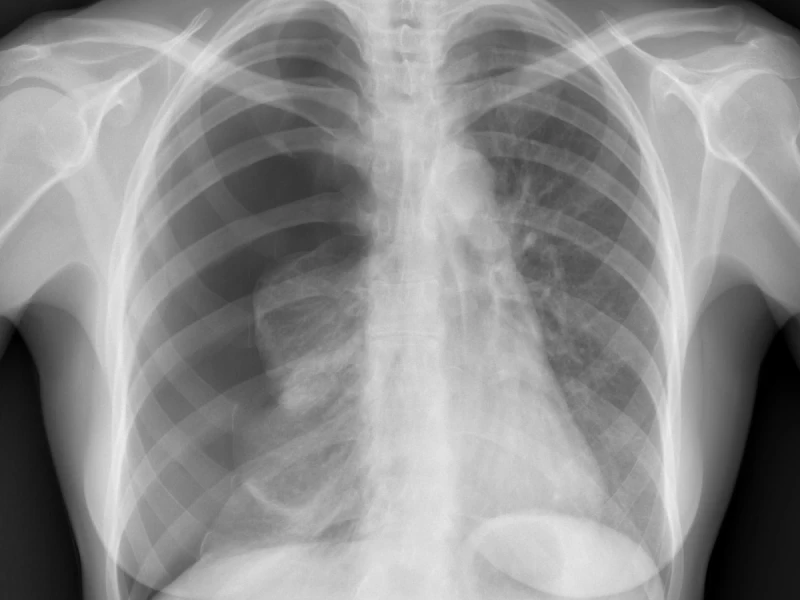

Consolidación del lóbulo inferior izquierdo

Consolidación del lóbulo inferior izquierdo Presentación Edad: N/A Género: Femenino Rx de tórax PA. Aumento…